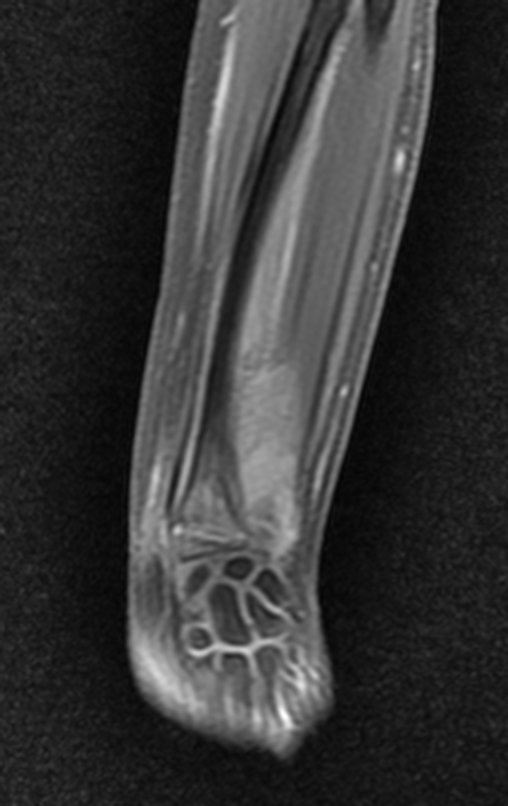

Después de una semana, el 14/08/2015, se retiró la férula y se encontró edema residual en la muñeca y dolor local. La semana siguiente, el 17/08/2015, fue evaluado por otro ortopedista quien repitió las radiografías y diagnosticó un quiste en el radio y una pequeña fractura arriba, figuras 1 a 5.

El domingo 20/09/2015, después de un día de mucha actividad física, caminar, nadar, se presentó aumento de edema y dolor en la muñeca derecha. Al día siguiente se realizaron nuevas radiografías de muñeca, que identificaron la evolución de la lesión, figuras 6 y 7.

Em 30 de maio de 2016, após seis meses de tratamento com Vimblastina EV, Mercaptopurina e Meticorten (50 mg) o paciente retorna para avaliação. Neste período teve um episódio de dor e edema do punho em Janeiro de 2016, cujas radiografias são apresentadas nas figuras 142 e 143. Manteve o punho imobilizado e reavaliou-se em 11-04-2016, figuras 144 e 145.